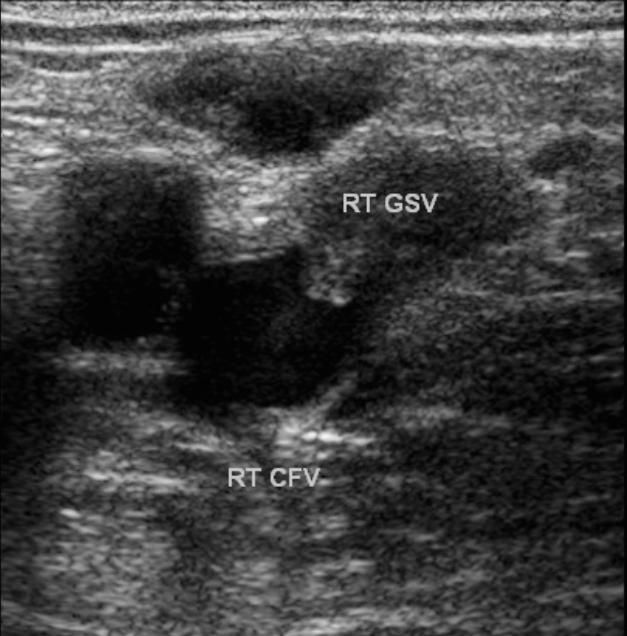

Bedside Ultrasound for Detection of Deep Vein Thrombosis: GSV = greater saphenous vein, PV = popliteal vein, DFV = deep femoral vein the correct images. Although the femoral vessels are large and relatively easy to locate, ... Fetch Document

The Saphenofemoral Junction In ultrasound - Schattauer GmbH

Opening of the great saphenous vein. The saphenofemoral junction is usually ensure greater clarity, the pudendal vein, which joins the great saphenous vein at the terminal val-ve, Both images are taken during muscular dias- ... Read Content